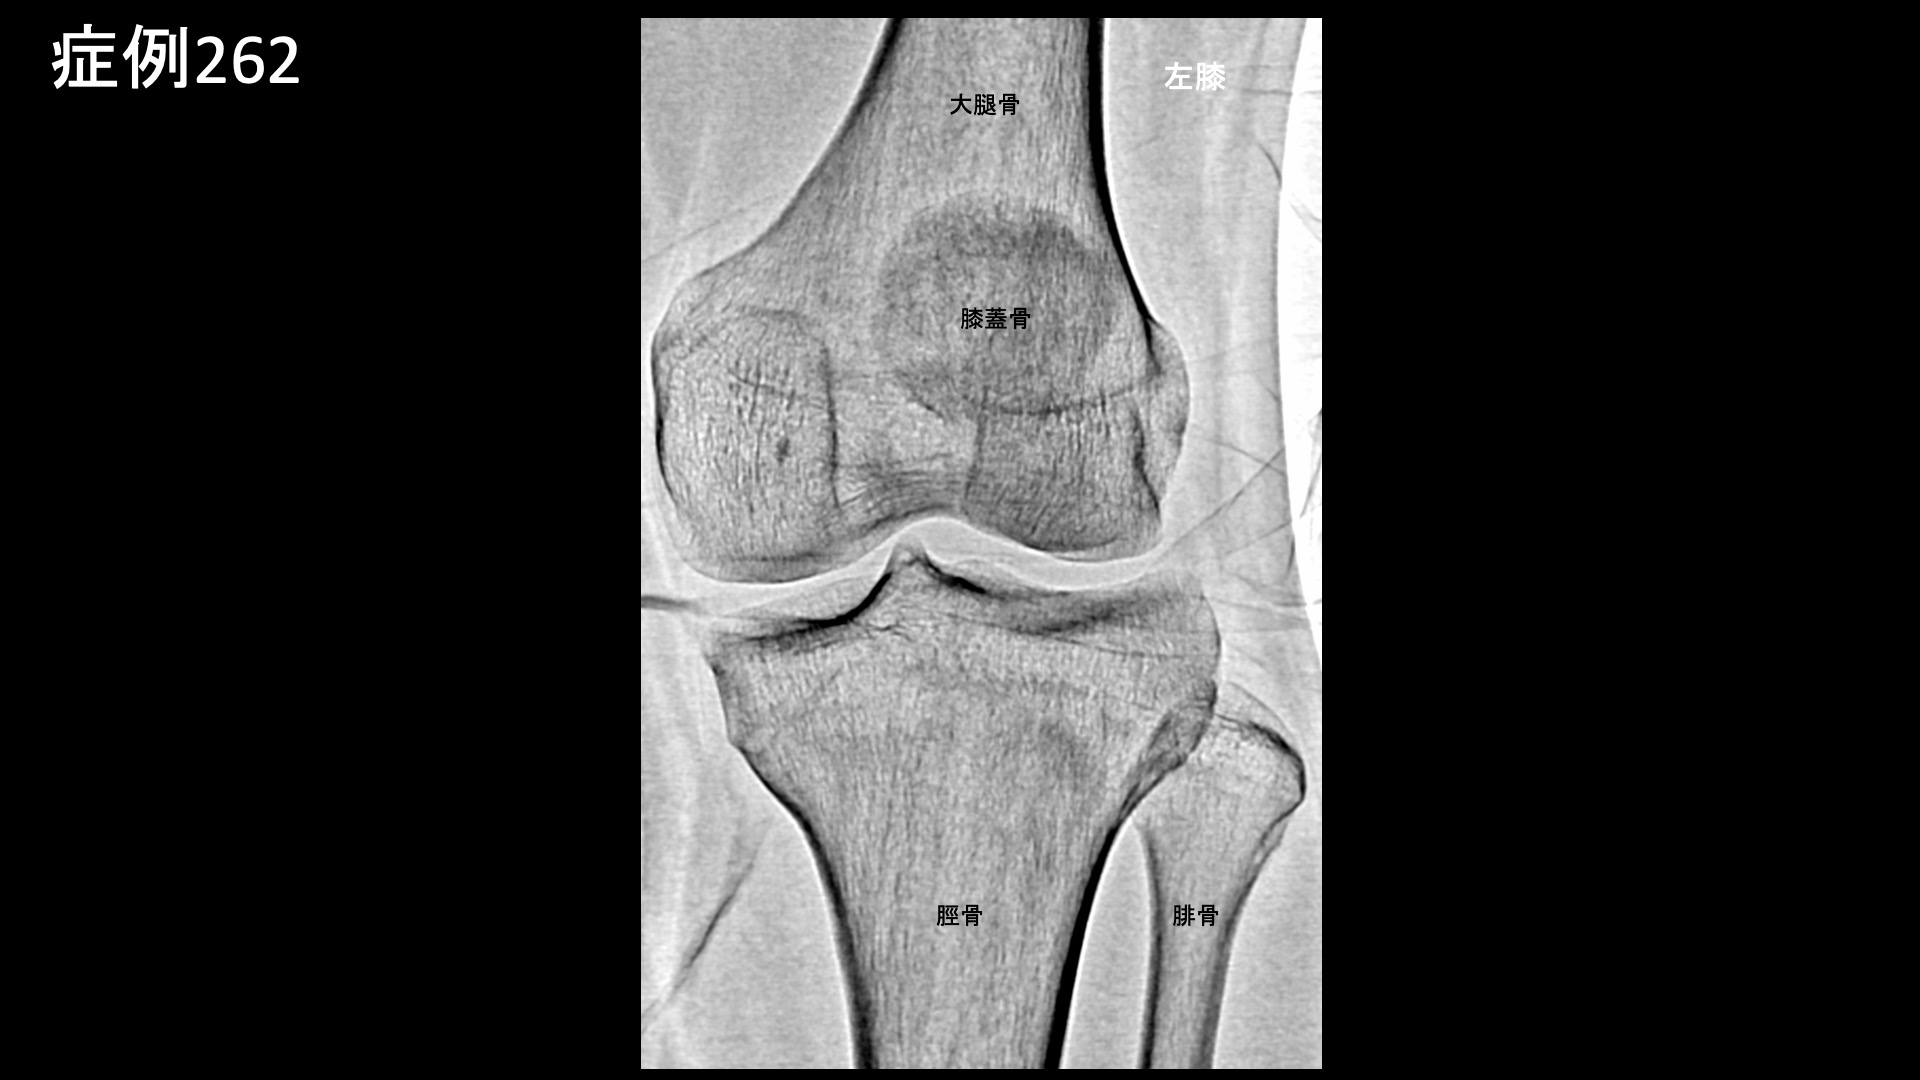

膝:変形性膝関節症など 【20代:男性】パフォーマンス向上のため、スケートボード選手が決断した後縦靭帯損傷後遺症に対するモヤモヤ血管治療(スケートボード、後縦靭帯損傷、外傷後遺症) 2026.02.13 鴨井院長による動画解説 受診までの経過 スケートボード選手です。1年半前から左膝の裏側の痛みがありました。左膝を立てると痛み、ぐっと曲げた時も痛みが増すが、正座までしてしまえば痛くありませんでした。MRI検査の結果、後縦靭帯損傷と診断され、保存的治療の方針となりました。日常生活や軽めの練習では問題ないものの、しっかり曲げられないと競技パフォーマンスを発揮できないことから、治療を決断し当院を受診されました。 診察時の所見 MRI検査にて上記のように確定診断後です。慢性痛に移行しており、モヤモヤ血管の治療適応と判断し、モヤモヤ血管(病的新生血管)に対する運動器カテーテル治療(微細動脈塞栓術)を受けていただきました。 治療の所見 血管造影を行うと、後縦靭帯の血行を担っている中膝動脈に一致して、モヤモヤ血管が濃染像として描出されました。前脛骨反回動脈においても同様にモヤモヤ血管が認められました。特徴的でありご本人に確認したところ、よく打撲する部位とのことでした。繰り返しの打撲により形成されたものと思われました。治療後、これらのモヤモヤ血管は画像上速やかに消失しました。尚、再現痛も一致していました。その他複数箇所の治療を行い終了しました。 *再現痛とは、薬液投与時に普段の痛みが一定程度再現される現象です。責任血管の同定のための参考とします。 治療前画像:損傷を受ける、あるいは繰り返しのストレスにより発生した異常な新生血管 治療後画像:カテーテルを用いて塞栓物質を血管内に投与し新生血管を塞いだ状態 治療費用:治療する部位によって費用が異なりますのでこちらをご参照ください。 主なリスク・副作用等:針を刺した場所が出血により腫れや痛みを生じたり、感染したりすることがあります(穿刺部合併症)。造影剤によるアレルギー(皮膚のかゆみ・赤み・息苦しくなるなどの症状)が出ることがあります。 治療後の経過 治療後2週間、数値で表すのは難しいが、いつも気になっていた部位の痛みが軽減され、問題なく競技ができているとのことでした。治療後1ヶ月半、ぐっと曲げた時に痛むことがなくなりました。転倒した時に気になる痛みもあったのですが、それもあまり痛まなくなりました。十分な練習ができるようになり、パフォーマンスも良好とのことでした。治療後3ヶ月、転倒時の痛みも無くなり、すこぶる調子が良いとご報告いただきました。経過良好であり終診としています。 スポーツ選手の場合、日常生活では困っていないが、競技パフォーマンスに支障をきたす痛みであるということが少なくありませんが、まさにそうした症例であり、パフォーマンスの向上に奏効しました。外傷後の後遺症はモヤモヤ血管治療の良い適応です。中々他に手立てがなくお困りの方も多いと思いますので、ご参考にしていただければと思います。 【60代:女性】発症2ヶ月の帯状疱疹後神経痛(鳩尾~乳房下~背中の痛み)に対するモヤモヤ血管治療(帯状疱疹後神経痛) 前の記事 【50代:女性】顔面に生じた難治の痺れと痛み、顔面骨折に三叉神経第2枝損傷を合併した外傷後疼痛に対するモヤモヤ血管治療(外傷後疼痛、顔面骨折、三叉神経第2枝損傷) 次の記事